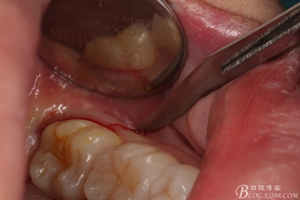

圖6.麻醉效果確定后,在37的近中做垂直松弛切口+遠中水平切口

圖7. 遠中的水平切口